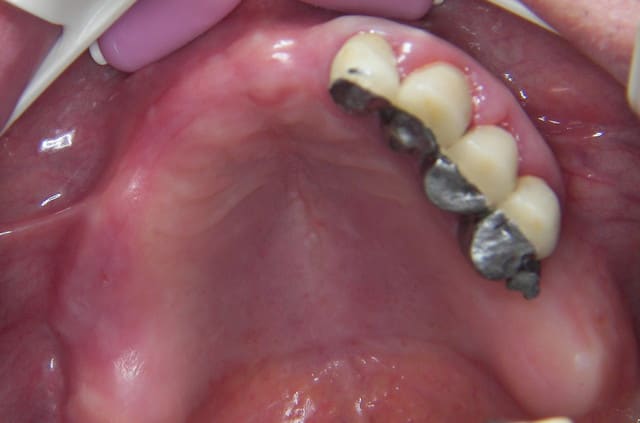

photos de la bouche au départ

100 4442r ro8hie - Eugenol

100 4473r hvl501 - Eugenol

100 4446 o2upvt - Eugenol